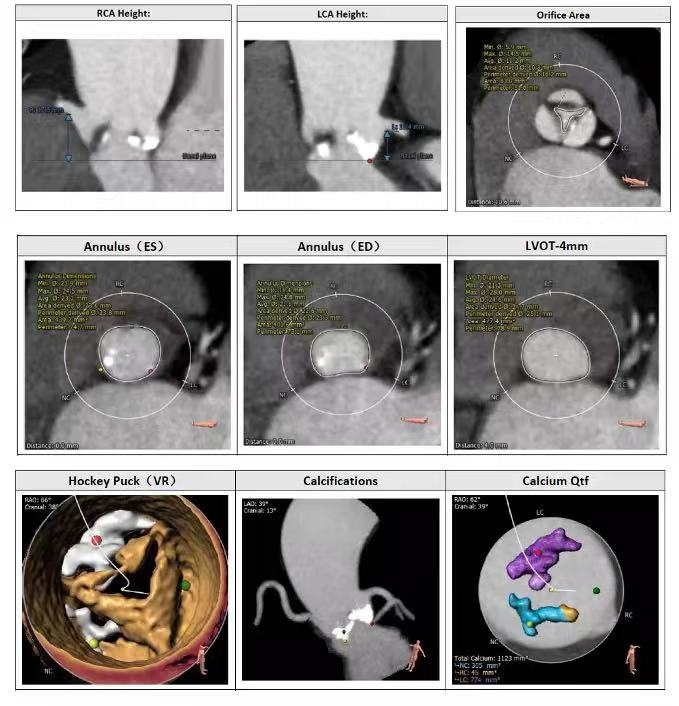

患者为女性,80岁,反复胸闷气喘1月伴一般体力活动受限。影像学检查提示二叶式主动脉瓣增厚伴重度钙化,主动脉瓣瓣口面积0.6cm²,平均跨瓣压差42mmHg,主动脉瓣瓣口峰值流速高达4.1m/s,同时合并中度主动脉瓣反流。

CT提示二叶式主动脉瓣明显钙化伴重度狭窄